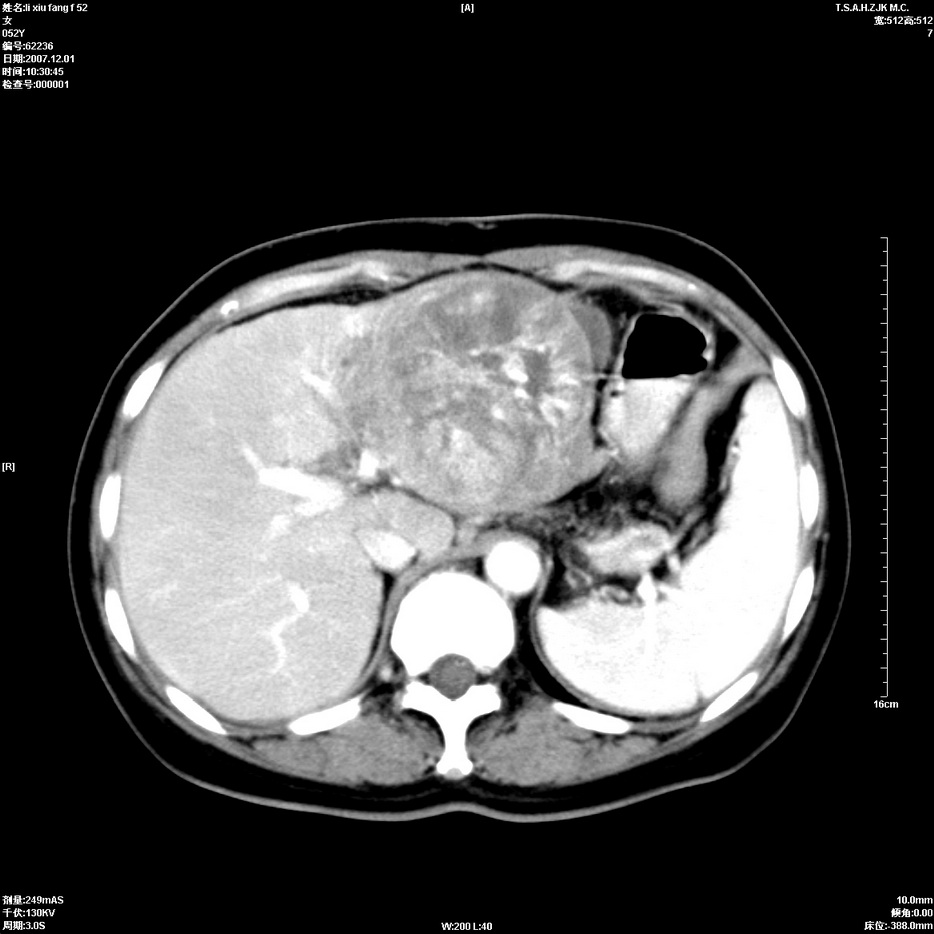

标题: CT12858:女,52岁,胎甲球蛋白861肝左叶占位,肝癌。下腔静 [打印本页]

标题: CT12858:女,52岁,胎甲球蛋白861肝左叶占位,肝癌。下腔静

肝左叶巨大低密度灶肿块,增强符合快进快出表现,有动静脉交通支;静脉期,下腔静脉内有充盈缺损,afp明显升高,支持肝癌并下腔静脉癌栓形成。

以下是引用拾荒者在2008-4-15 22:57:00的发言:[br]肝左叶巨大低密度灶肿块,增强符合快进快出表现,有动静脉交通支;静脉期,下腔静脉内有充盈缺损,afp明显升高,支持肝癌并下腔静脉癌栓形成。